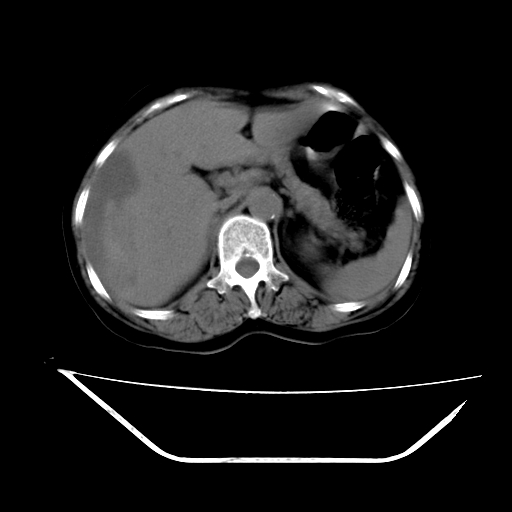

2008-11-10ct平扫(其间去中山医院诊治未行特殊治疗)

2008-11-10ct平扫见并肝内、血膜下血肿基本吸收,肝内低密度灶缩小。此时再做增强ct应有显着意义。对患者/医者都好!

从平扫+增强及治疗后复查片,病变明显缩小,不考虑肝癌出血可能,还是考虑为良性病变可能性大;单纯血肿并包膜下积液吧,病变强化没法解释,肝血管破裂出血吧,增强不符合典型血管瘤的表现,良性肿瘤破裂出血吧,复查片看来好像也不太支持(没做强化也不太好说)。本人还是考虑单纯肝内血肿并包膜下积液,强化是不是血管有外渗。

患者自6月至11月,如果是肝癌,没有经过特殊治疗,想必应该会有所进展吧,而不是ct所见,反而似有病灶减小的趋势。建议增强。